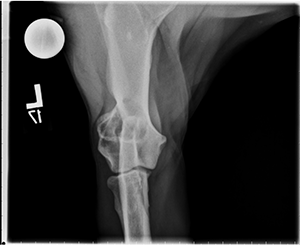

11-year-old dog with limp

Radiographs of the left elbow show the following:

Cranial-caudal view: